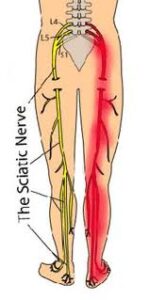

10 këshilla për të përmirësuar ishiasin (ervin ishiatik – Ischialgia) Ishiasi (nervi ishiatik) shkaktohet prej ngacmimit ose dëmtimit të nervit ishiatik – nervi më i

10 këshilla për të përmirësuar ishiasin (ervin ishiatik – Ischialgia) Ishiasi (nervi ishiatik) shkaktohet prej ngacmimit ose dëmtimit të nervit ishiatik – nervi më i

Dhimbja e nervit ishiatik është dhimbje e ekstremiteteve te poshtme që rezulton si pasoje e ngacmimit të nervit ishiatik. Dhimbja e nervit ishiatik ndjehet ne menyre tipike ne